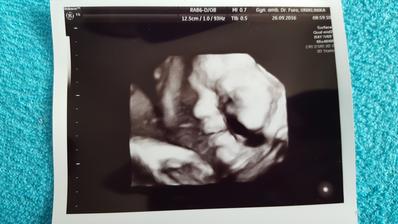

26.09.2016 : posledná poradňa u môjho gynekológa